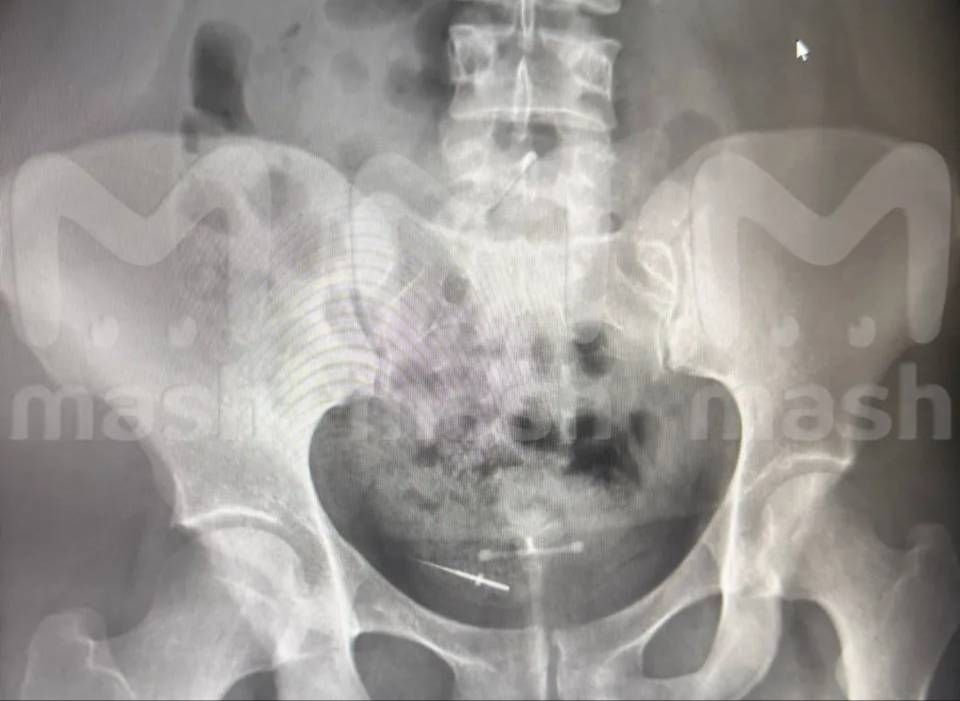

Пациентка стоматолога нашла протейпер в кишечнике после приёма в Башкирии. Вероятно, она проглотила инструмент для обработки каналов во время процедуры.

Сразу после лечения зубов 26-летняя девушка почувствовала острую боль в животе. Она сделала рентген — к тому времени протейпер уже мигрировала в нижнюю часть туловища.

Стоматолог уверяет, что никакие инструменты не теряла, её пациентке придётся идти на операцию.